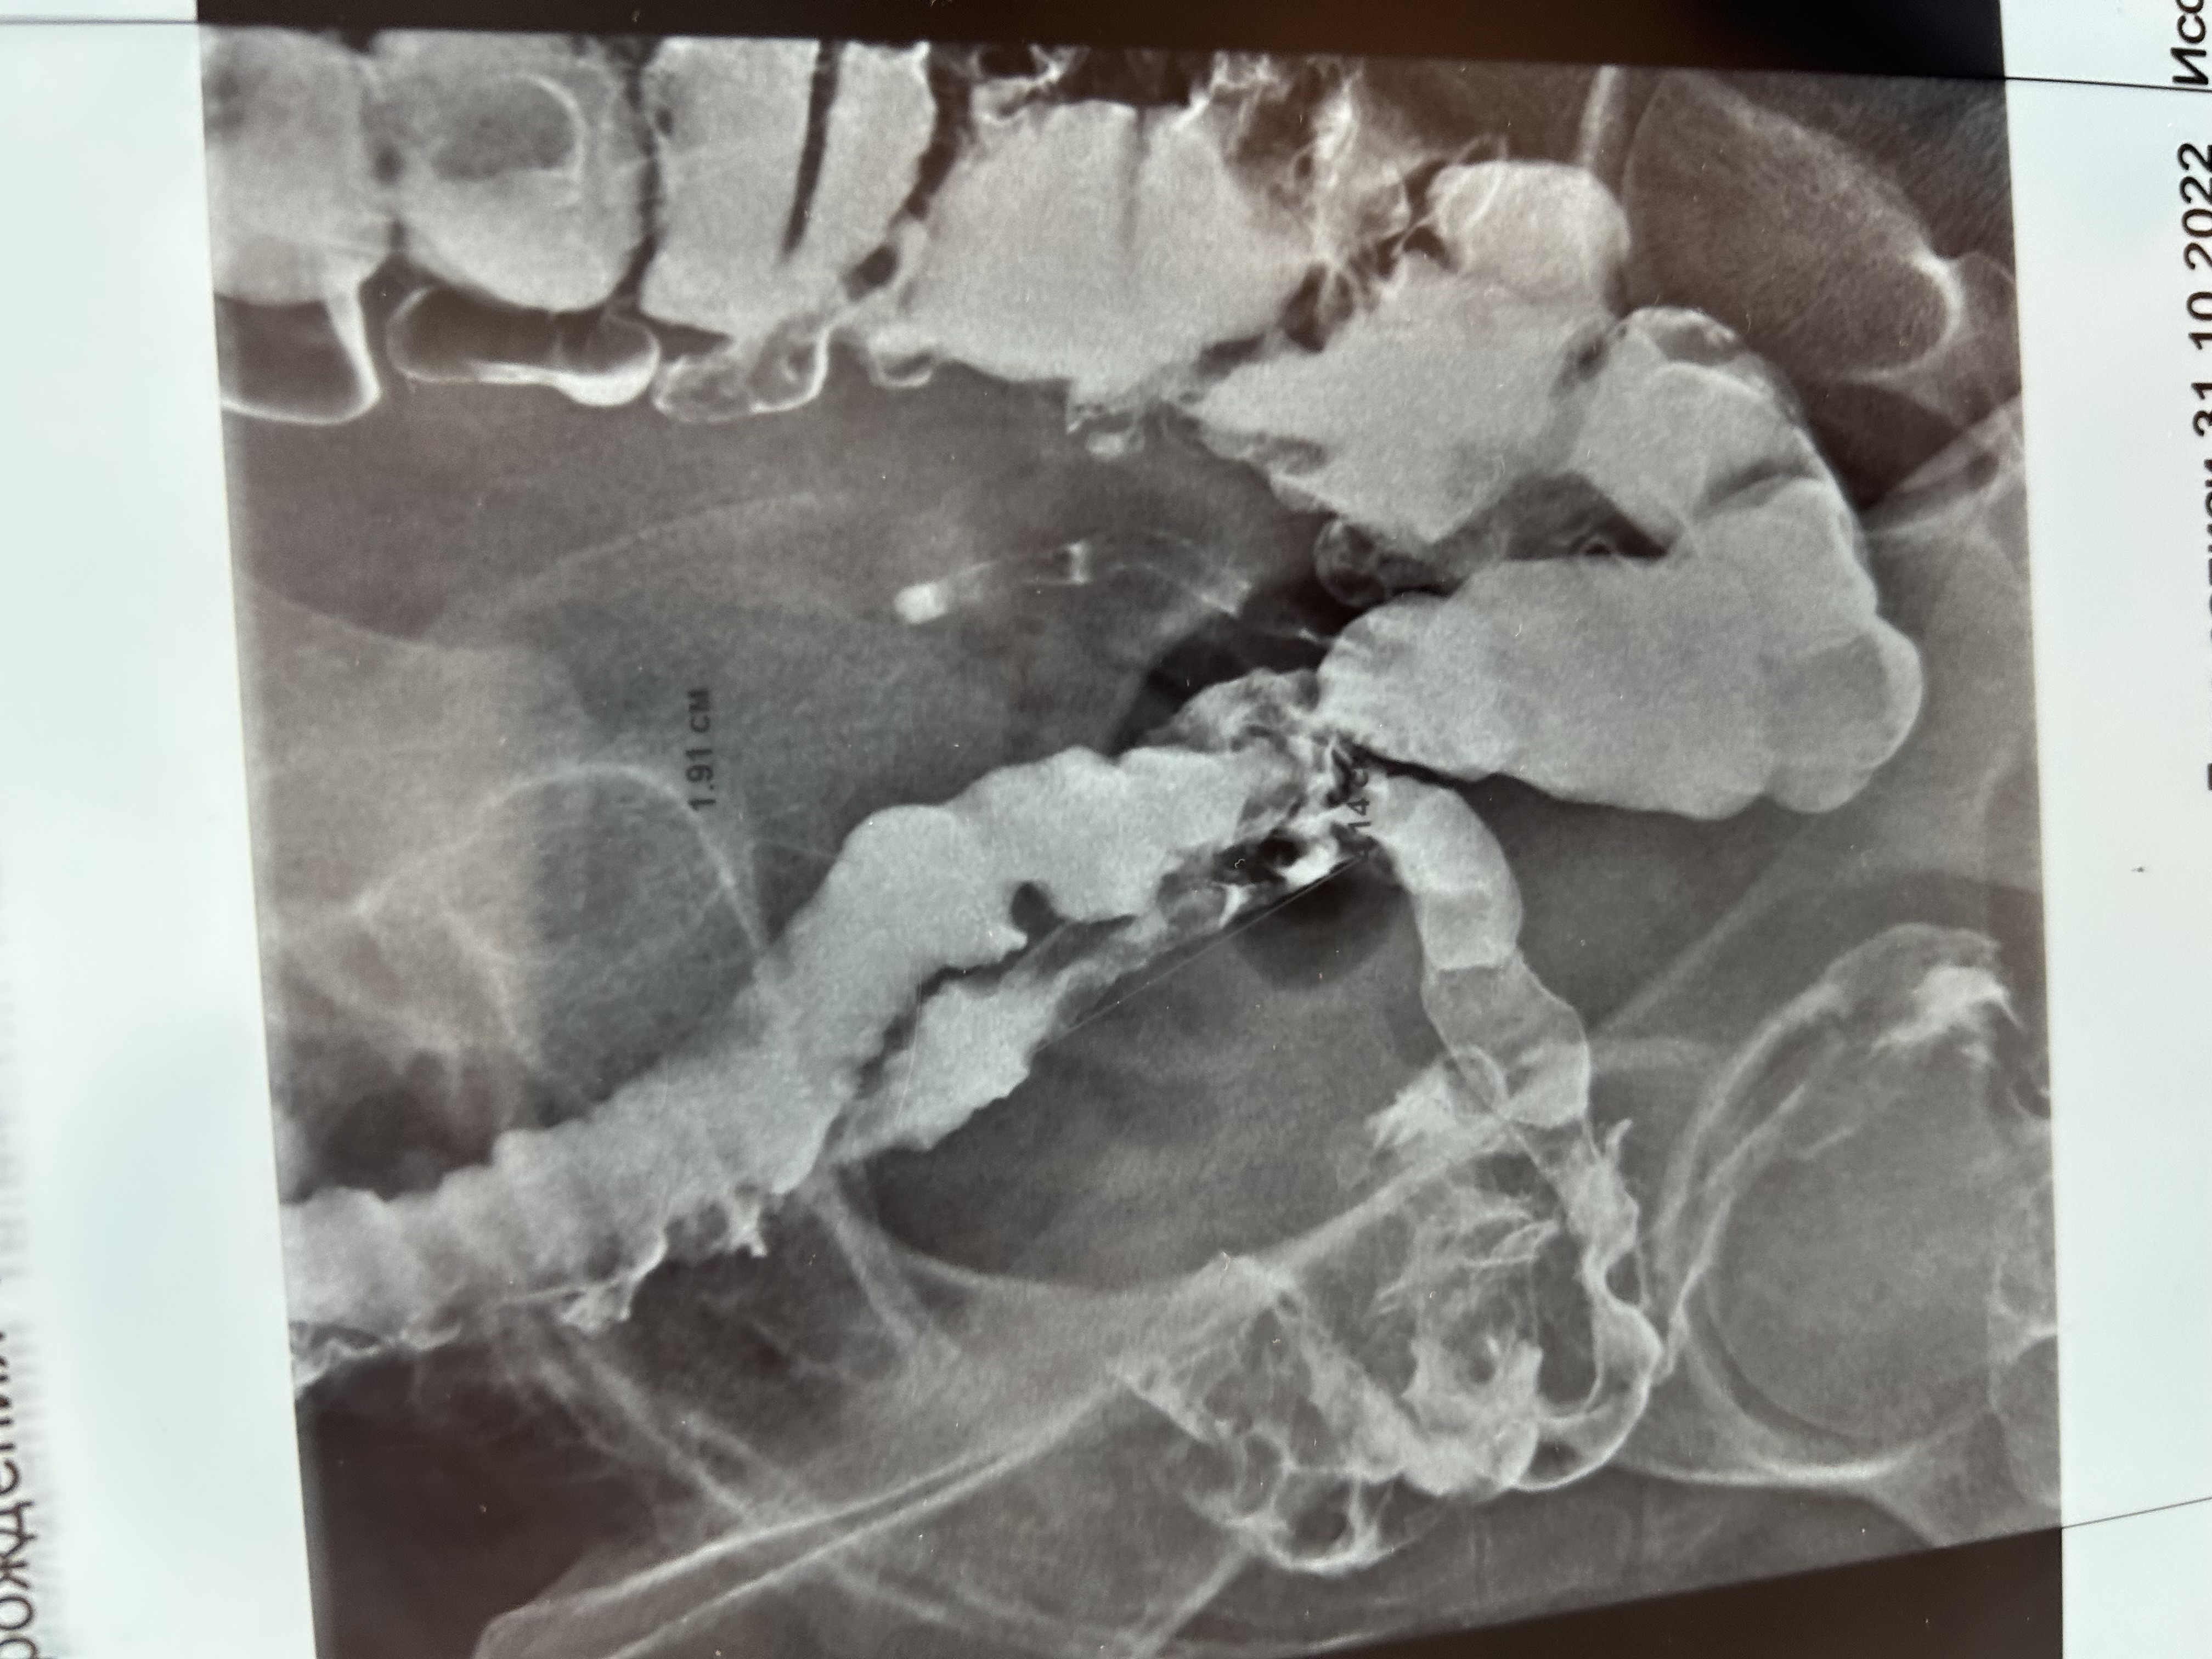

«Она долгое время ходила по разным врачам и ей не могли долго поставить диагноз, потому что когда она обращалась к гинекологам, то они, понятно, отсылали ее к хирургам, поскольку у нее во время месячных выделялась из прямой кишки алая кровь. Надо было исключить онкопатологию и выявить очаг эндометриоза в кишке. Но хирурги, к сожалению, долго не могли выявить патологию ни по данным МРТ, ни видеоколоноскопии. И только в 7 горбольнице, проведя ренгенконтрастное исследование кишечника не только нашли этот очаг эндометриоза, но и установили, что он сужает просвет кишки, - рассказывает врач – акушер-гинеколог, профессор Казанского медуниверситета, научный куратор гинекологов нашей клиники Рушанья Исмагиловна Габидуллина. - И вот еще одна была серьезная проблема – у нее бесплодие, она никак не могла забеременеть. И, к сожалению, мы не могли ее отправить на ВРТ, потому что у нее был стеноз кишки».